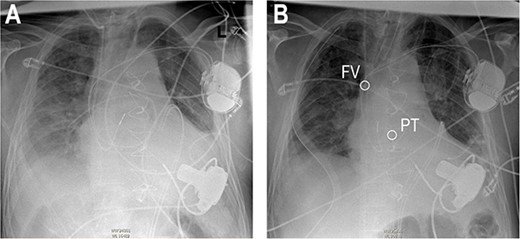

Anteroposterior thoracic radiography after LVAD implantation (A). Anteroposterior thoracic radiography after RVAD cannulation of the PT (B). Tip of cannula in the right FV, tip of cannula in the PT.